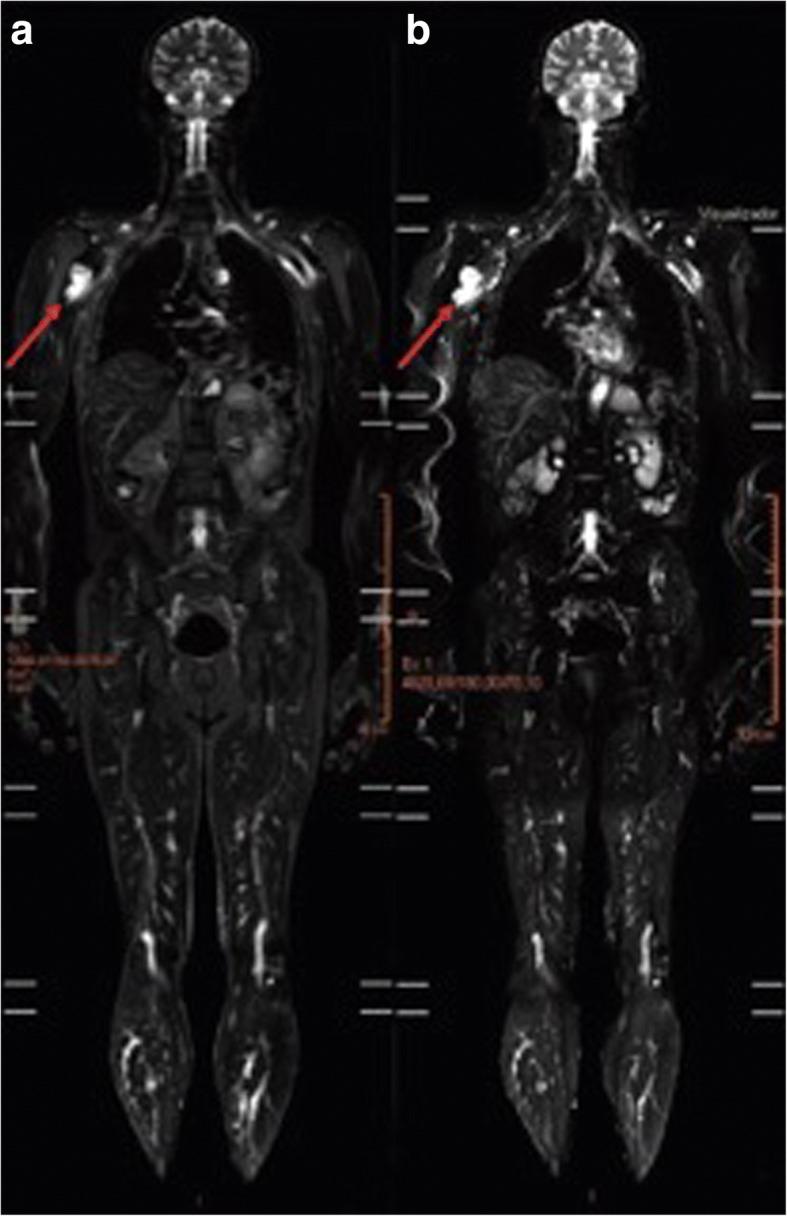

Li-Fraumeni syndrome (LFS) is an autosomal dominant disease that is associated with germline TP53 mutations and it predisposes affected individuals to a high risk of developing multiple tumors. In Brazil, LFS is characterized by a different pattern of TP53 variants, with the founder TP53 p.R337H mutation being predominant. The adoption of screening strategies to diagnose LFS in its early stages is a major challenge due to the diverse spectrum of tumors that LFS patients can develop. The purpose of this study was to evaluate two rounds of whole-body magnetic resonance imaging (WB-MRI) which were conducted as a screening strategy for LFS patients.

Over a 4-year period, 59 LFS patients underwent two rounds of WB-MRI. Each MRI was characterized as positive or negative, and positive cases were further investigated to establish a diagnosis. The parameters used to evaluate the WB-MRI results included: positive rate, number of invasive investigations of positive results, and cancer detection rate.

A total of 118 WB-MRI scans were performed. Positive results were associated with 11 patients (9.3%). Seven of these patients (11.8%) were identified in the first round of screening and 4 patients (6.7%) were identified in the second round of screening. Biopsies were performed in three cases (2.5%), two (3.4%) after the first round of screening and one (1.7%) after the second round of screening. The histopathological results confirmed a diagnosis of cancer for all three cases. There was no indication of unnecessary invasive procedures.

WB-MRI screening of LFS carriers diagnosed cancers in their early stages. When needed, positive results were further examined with non-invasive imaging techniques. False positive results were less frequent after the first round of WB-MRI screening.